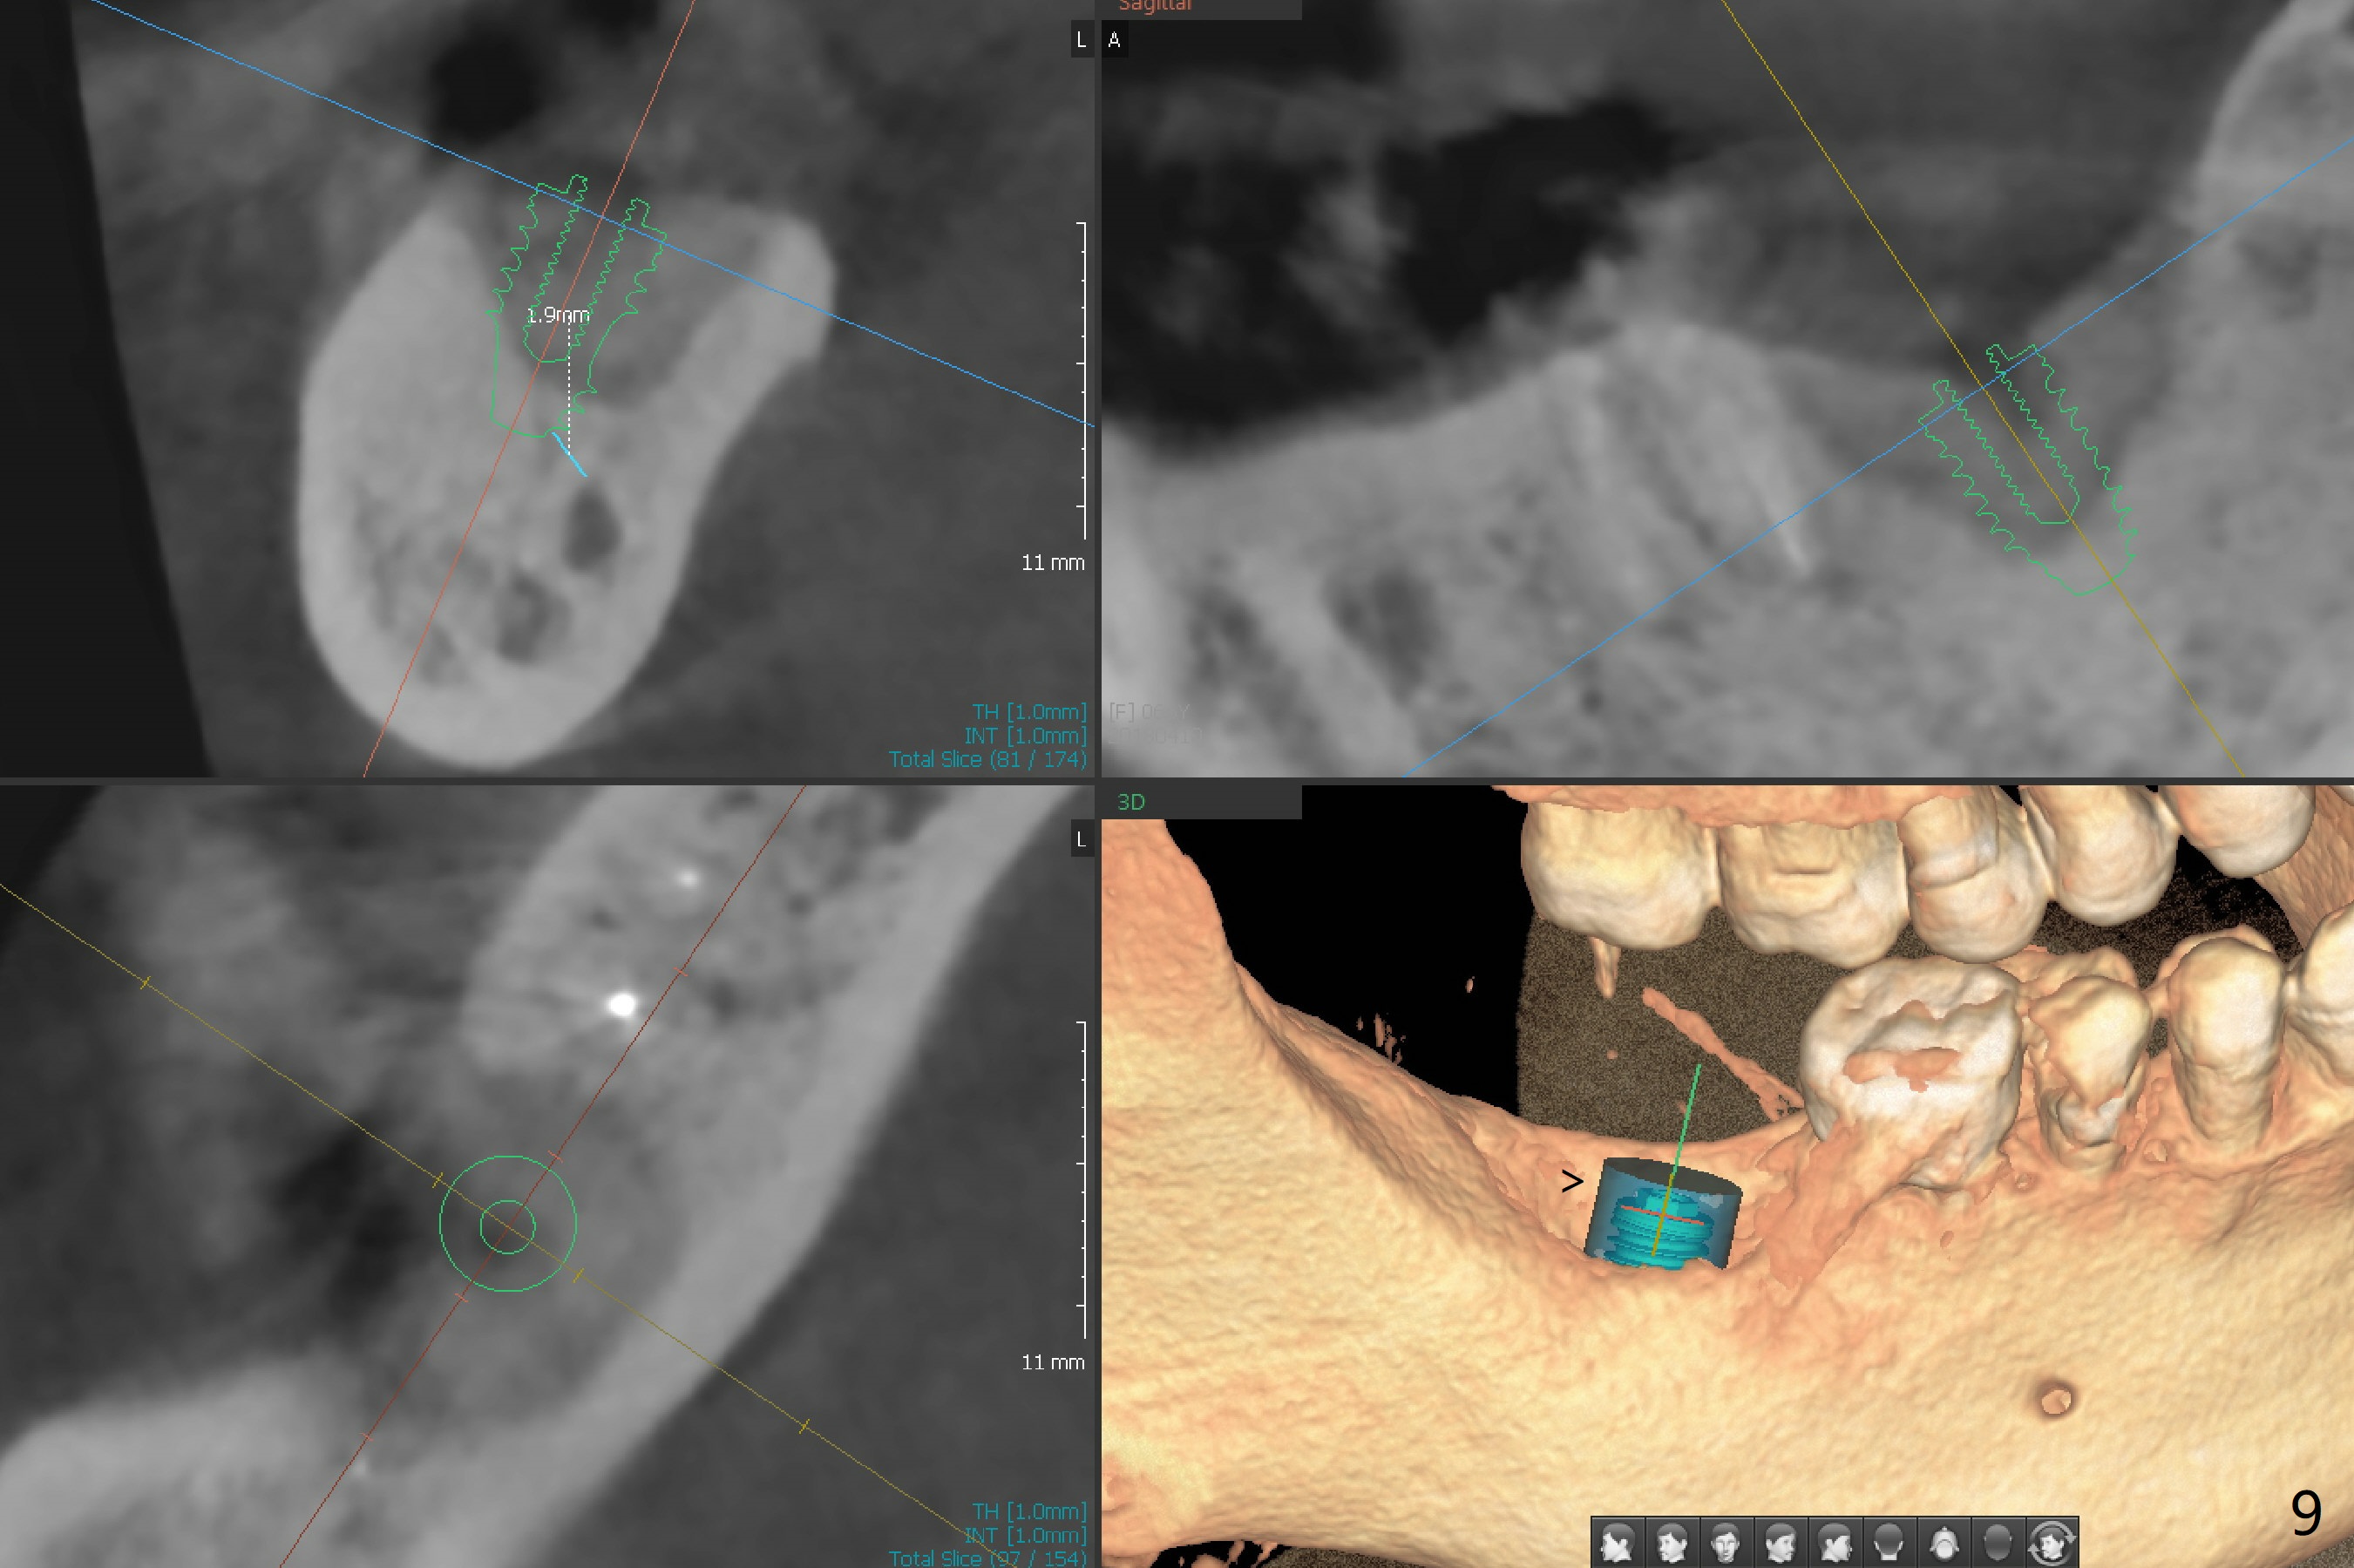

There is a mesiobuccal fistula at #31 with periimplantitis (Fig.1 ^). The bone loss is severe before and after implant removal (Fig.2). It is impossible to place bone-level implant in the original osteotomy due to insufficient bone height. There is pain when a new osteotomy is being initiated in the mesial slope. Following placement of Vera Graft (Fig.3), collagen plug and 6-month resorbable membrane, the wound is closed with suture (mild tension). Postop, there is oozing. Periodontal dressing should have been applied. If the ridge can be preserved in 4-6 months, a 11 mm long implant (Fig.4 green line with 4 mm of the native bone) can be placed with 1.9 mm clearance (red dashed line: the superior border of the Inferior Alveolar Canal); the abutment is estimated to have 4 mm cuff (pink). The socket appears to be healing 8 days postop (Fig.5). The ridge remains wide 5 months post implant removal, although the bone density is low (Fig.6,7 (still ~ 1000 units). It seems that a 5x11.5 mm implant could be placed in the mesiobuccal aspect of the bony defect (Fig.8). For better occlusion, the implant should be shorter (5x8.5 mm) after discussion with the guide lab (Fig.9). Make sure that the most coronal thread is buried by the bone graft, i.e., underneath the crest(>).